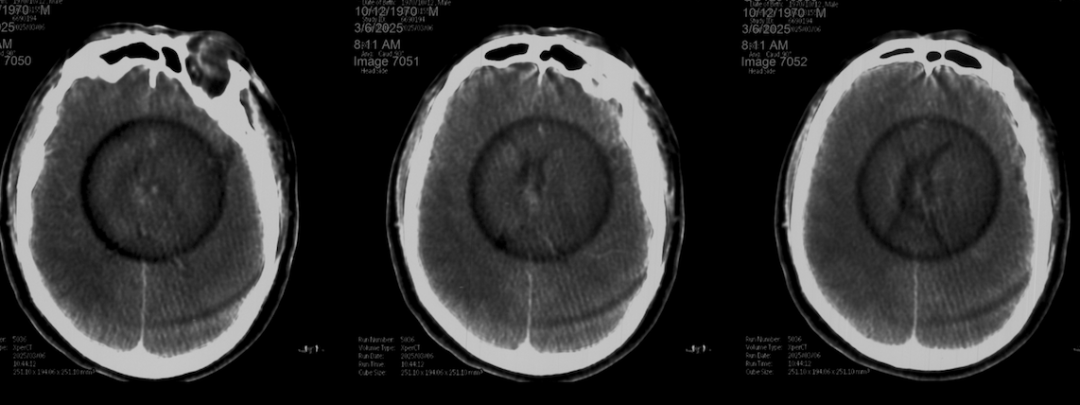

术后正侧位造影:Raymond Ⅲ级

术后支架重建:支架打开良好,近端Marker位于颈内动脉分叉处

术后Vaso CT未见出血,患者神清语利,神经系统查体阴性。